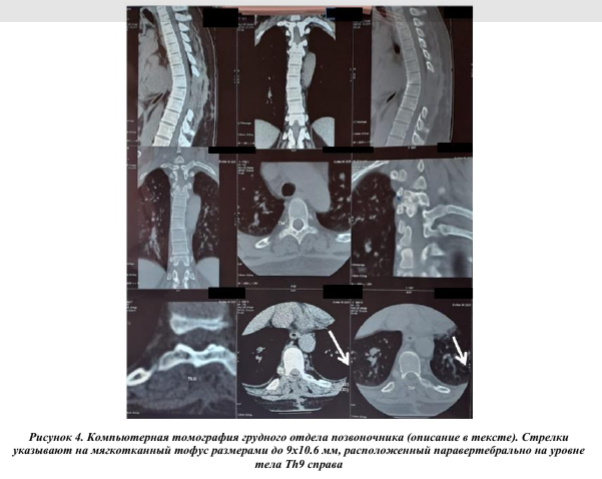

На серии МСКТ грудного отдела позвоночника - состояние после ламинэктомия TH6- TH9, парциальной костотрансверзэктомия в сегментах TH6 - Th7 позвонков с двух сторон, субтотальная резекция объемного образования с декомпрессией спинного мозга; ось позвоночного столба изменена, сколиоз, угол открыт влево, усиление физиологического кифоза; на момент исследования определяются участки кистовидной трансформации с четким склеротическим ободком, частично вскрышегосятипа с поражением дуги, поперечного отростка Th4 справа в сочетании поражением с дуго-отросчатого сустава Th4-Th5 справа с признаками артрита; аналогичные изменения в проекции дуги Th10 справа; паравертебрально на уровне тела Th9 справа определяется мягкотканый тофус размерами до 9х10,6 мм; обращает внимание значительный неравномерный субхондральный склероз замыкательных пластин, в сочетании со значительным неравномерным гиперостозом по периметру смежных замыкательных пластин; межпозвонковые диски умеренно равномерно уплощены, без значимых протрузионных изменений, в том числе в сторону СМК и межпозвонковых каналов; патологических изменений в превертебральных мягких тканях не выявлено, неравномерное умеренное уплотнение в зоне оперативного доступа (Рис.4). В последнее время в литературе стали чаще встречаться описания поражения позвоночника вследствие роста тофусов у больных подагрой, в том числе и в молодом возрасте [6,7,8]. Причины образования тофусов в позвоночном столбе не установлены. Изучается значение таких факторов, как вы сокая гиперурикемия, сниженная почечная функция, дли тельность болезни, возраст, количество атак острого артрита [9].